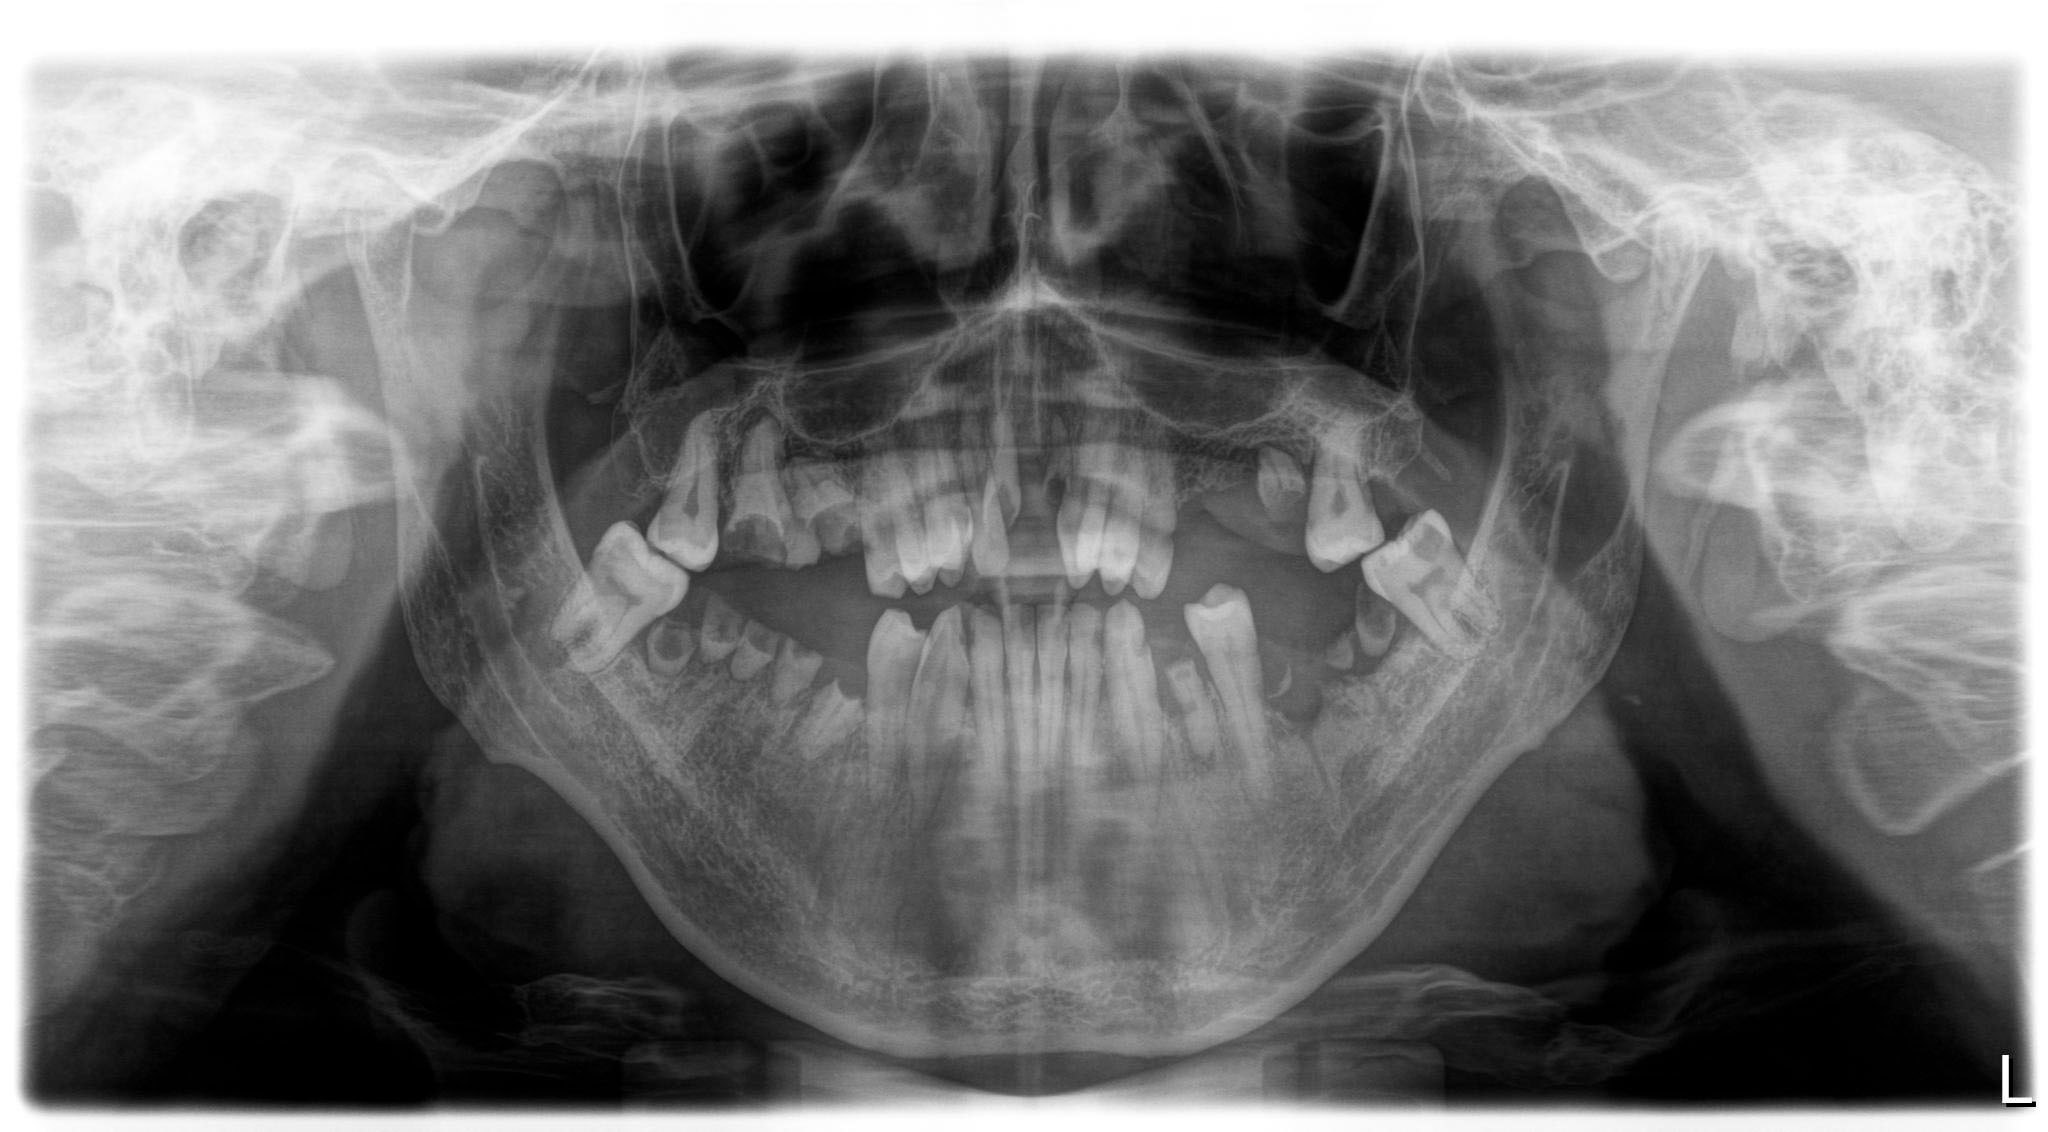

Fornecemos exames radiologicos internamente (você não precisa se deslocar)